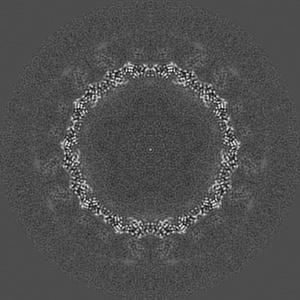

The cryo-EM structure of HAV bound to a neutralizing antibody-F4

Structural basis for neutralization of hepatitis A virus informs a rational design of highly potent inhibitors.

Cao L , Liu P , Yang P , Gao Q, Li H, Sun Y , Zhu L, Lin J, Su D, Rao Z, Wang X

(2019) PLoS Biol , 17 , e3000229 - e3000229